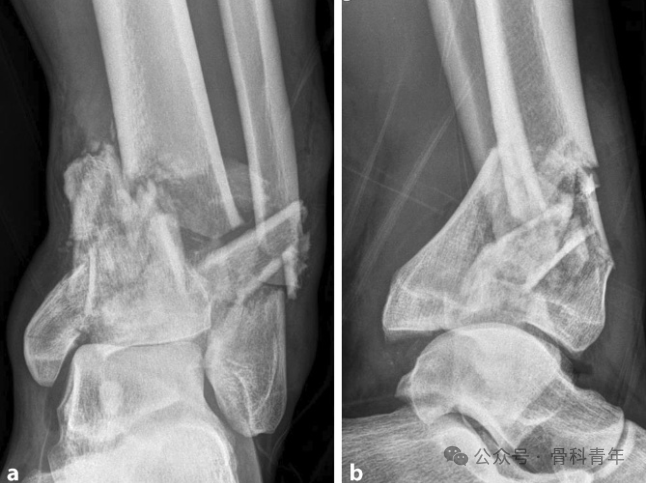

固定(Span):实施跨关节外固定架固定术;